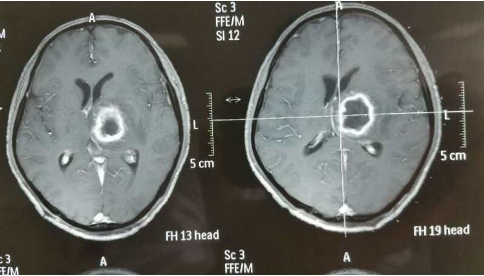

患者黄ⅹx,男,43岁,患有严重的先天性心脏病,因"左侧丘脑脑脓肿"入院。心功能差,不能耐受其他任何麻醉,且病灶小、位置深、手术风险大,患者恐惧心里明显,只能选择行"CT引导微创穿刺脑脓肿引流术"。今天上午,脑外一科主任、主任医师杨先清亲自主刀,顾磊医生密切配合,手术在局麻下进行,头皮5mm穿刺口,精准定位,一次性穿刺成功,抽出5mⅠ脓液,抗生素反复冲洗脓腔至清澈为止,手术顺利。术中患者意识清楚,全程能和术者交流。术毕,安返病房。

脑脓肿是一种严重的颅内感染性疾病,使脑组织及结构受到严重破坏,造成部分患者相关神经机能发生不可逆性损伤及永久性障碍,甚至危及患者生命。

微创是以最小的创伤获得最好的或是同等的疗效,是外科领域的发展方向。具有安全、简便、创伤小、患者痛苦小、疗效可靠、适应范围广等优点。

微创技术是六安市中医院脑外一科杨先清主任1999年开始在皖西地区率先开展,技术处于领先地位。目前该项技术已广泛应用于高血压性脑出血、深部脑脓肿、慢性硬膜下血肿、囊性颅咽管瘤等颅内疾病的治疗。其中 "CT引导微创置管技术在神经外科的应用"更是在2013年获市科技进步二等奖。